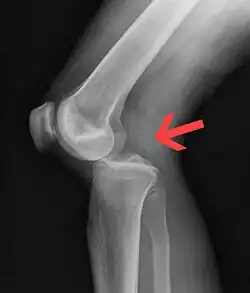

Plain X-rays, CT scan, ultrasonography, or MRI may help with the diagnosis.[2][11] Findings on X-ray that may be useful among those who have already reduced include a variable joint space, subluxation of the joint, or a Segond fracture.[5]

They may be divided into five types: anterior, posterior, lateral, medial, and rotatory.[4] This classification is based on the movement of the tibia with respect to the femur.[11] Anterior dislocations, followed by posterior, are the most common.[2] They may also be classified on the basis of which ligaments are injured.[2]